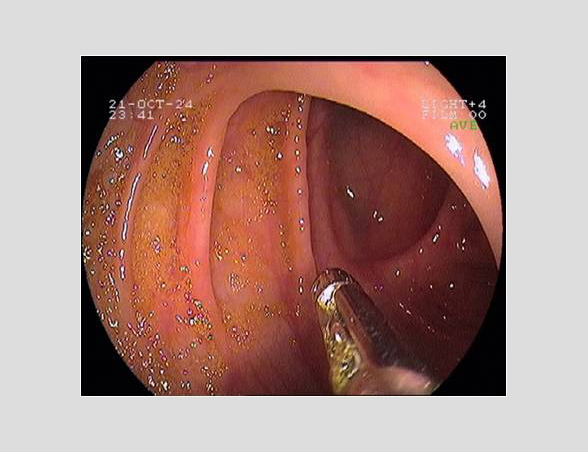

Imágenes tomadas durante la endoscopia digestiva alta y la colonoscopia. Se aprecia una mucosa de aspecto y vascularización normal, sin lesiones visibles. Se progresa con el colonoscopio hasta el íleon. Todo resulta macroscópicamente normal. Se toman biopsias de todos los segmentos explorados.

Pruebas complementarias: panendoscopia oral y colonoscopia

La endoscopia es el método de elección para el diagnóstico y seguimiento de la EII. Permite una visión macroscópica de la mucosa intestinal y la toma de múltiples biopsias para el estudio histológico.

En todos los pacientes en los que se sospeche una EII está indicada la realización de una colonoscopia completa con ileoscopia y una endoscopia digestiva alta.

Es la técnica de elección para diferenciar entre colitis ulcerosa (CU) y enfermedad de Crohn (EC), así como para localizar y valorar la extensión de la enfermedad.

Realizamos una endoscopia digestiva alta y una colonoscopia a la paciente con toma de biopsias, obteniendo el informe de Anatomía patológica.